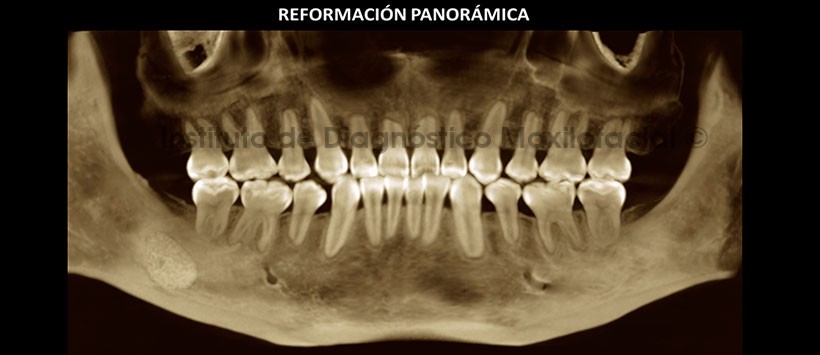

En la reformación panorámica de la tomografía volumétrica (Figura 1) se aprecia reabsorción radicular externa del tercio apical de las piezas 1.2, 1.1, 2.1, 3.5 y 4.5; Así mismo no se observa los gérmenes de las terceras molares así como la ausencia de todas las primeras premolares. Como hallazgo se puede apreciar la presencia de una raíz supernumeraria a nivel de las piezas 3.6 y 4.6.